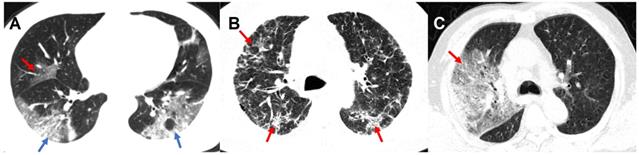

Chest CT scans were routinely performed using ≥ 16 slice multidetector CT scanners without use of contrast agents. Scanners and scanning protocols in details can be found in Supplementary materials. All Digital Imaging and Communications in Medicine (DICOM) images were reviewed by four radiologists (Z.Y.S, L.Q, F. X. and J. Z.) with 18, 6, 5 and 5 years of experiences in thoracic radiology in core lab in Jinling Hospital, Medical School of Nanjing University, respectively. They independently evaluated initial CT images without access to patient's clinical or laboratory results. The following CT features were analyzed and recorded: lesion distribution, morphology and number of lesions; main signs including pure ground-glass opacity (GGO), pure consolidation, GGO with consolidation, interstitial lung disease (ILD), crazy-paving pattern and other abnormalities. The number of affected lung lobes and lung segments were recorded (Supplementary Materials). We also proposed a lung segment-based CT severity score to assess the severity of the pneumonia. Some representative CT signs are shown in Figure 2 and more detailed CT image features are summarized in Supplementary Materials. Any disagreement was resolved through discussions and consultations.

Figure 2

Representative CT Images of confirmed COVID-19 pneumonia. Panel A: A 46-year-old male patient presented with fever, cough, and fatigue without a clear exposure history. Irregular GGO (red arrow) can be seen in the middle lobe of the right lung, and large patchy irregular GGO with consolidation (blue arrow) can be seen in the lower lobes of both lungs. Panel B: A 56-year old male patients presented with fever, cough, fatigue and headache without a clear exposure history. Extensive diffuse pneumonia can be seen in both lungs with multiple ILD (red arrow). Panel C: A 62-year-old male patients presented with fever, cough, myalgia as well as diarrhea, and had a close contact with confirmed COVID-19 patients. In the context of GGO with consolidation, crazy-paving pattern (red arrow) can be seen in the right lung. COVID-19: Coronavirus Disease-19; GGO: ground-glass opacity; ILD: interstitial lung disease.